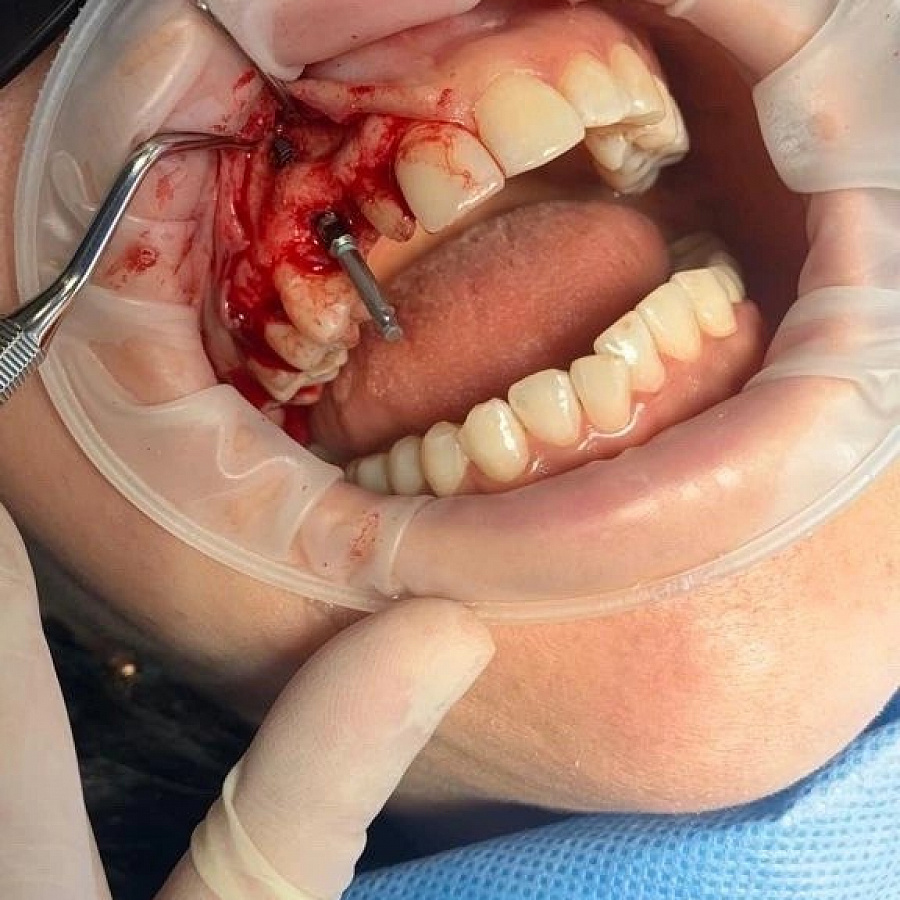

Удаление старого импланта и установка нового